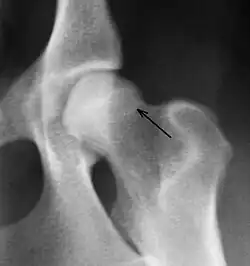

Sekundäre Kriterien sind Hinweise auf arthrotische Prozesse infolge der Fehlbelastung. Dazu gehören Verformungen und „Lippenbildung“ am Hüftkopf, walzenförmige Verdickungen des Oberschenkelhalses, Randwülste an der Gelenkpfanne, unter dem Knorpel befindliche Verdichtungen der Knochensubstanz im Pfannenbereich und die Anlagerung von Knochenmaterial (Osteophyten) am Ansatz der Gelenkkapsel (Morgan-Linie, caudodorsal curvilinear osteophyte, CCO). Die Morgan-Linie ist ein sensitiver Frühmarker für eine Instabilität im Hüftgelenk,[6] allerdings haben nicht alle Tiere mit einer Morgan-Linie auch eine Dysplasie oder Arthrose.[3]